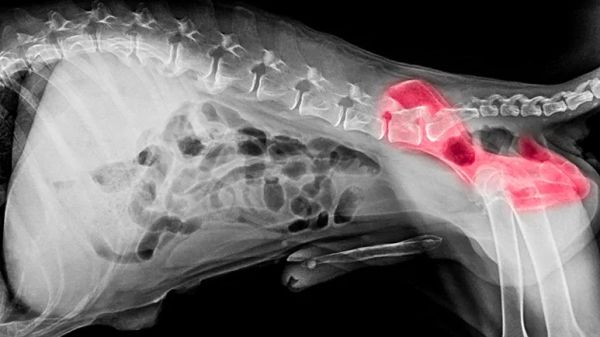

A dog with arthritis may limp, move slowly or have difficulty standing up after lying down. But what about the more subtle signs of degenerative joint disease that can affect dogs of all ages and sizes? When pet parents see these signs, they most likely wouldn't suspect joint disease, but should.